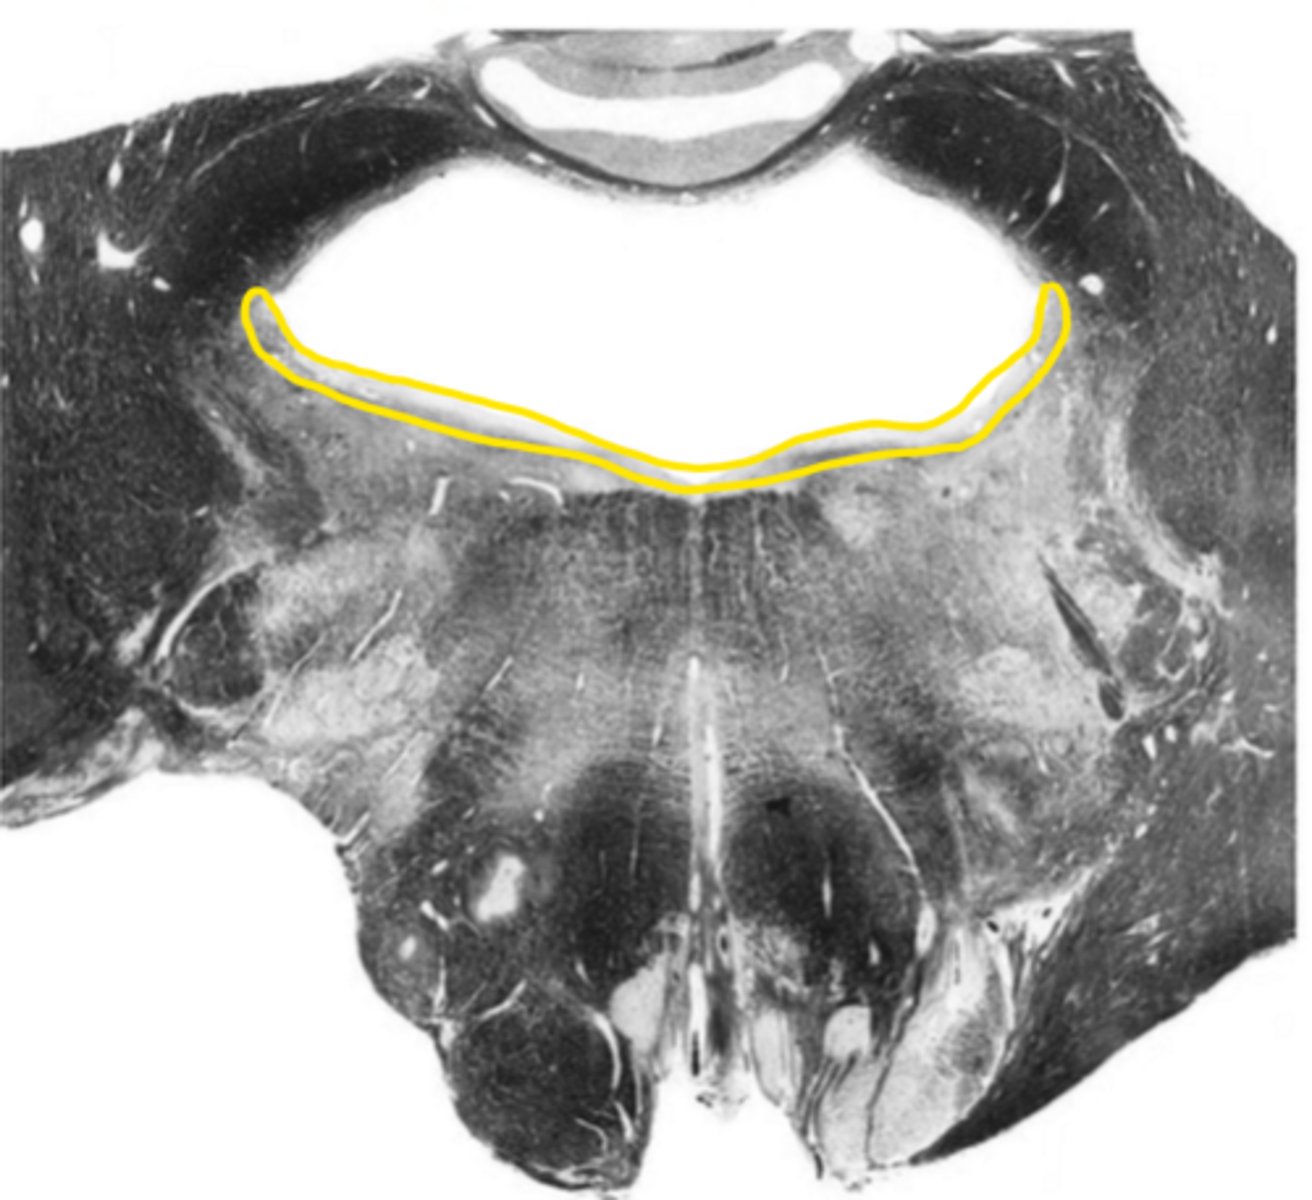

medial lemniscus

ID the structure